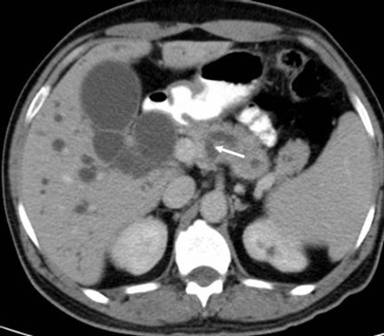

He underwent a pancreaticoduodenectomy. On transecting the neck of the pancreas, there was a small duct (4 mm) on the cut surface anterior to the portal vein. While dividing the bulky uncinate process, which seemed to extend posteriorly and to the left of the portal vein, a dilated duct (10 mm) was encountered. This dilated duct was found to be continuous with the main pancreatic duct posterior to the portal vein. The anterior duct in the neck of the pancreas terminated a few centimeters within the body of the pancreas without communication with the main pancreatic duct. The large pancreatic duct encountered in the uncinate process resection was closed with interrupted 5/0 polypropylene sutures. The neck of the pancreas anterior to the portal vein was excised up to the dilated main pancreatic duct, well to the left of the portal vein. The main pancreatic duct was laid open and a side to side pancreaticojejunostomy was performed. The patient made an uneventful recovery from the surgery. A review of the CT scan showed the double ducts encircling the portal vein with the main pancreatic duct lying posteriorly to the portal vein (Figures 1, 2, 3 and 4).

Figure 2. Main pancreatic duct dipping posteriorly to course around the portal vein highlighted by white arrows. |